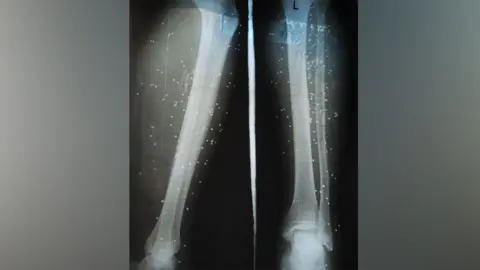

Surgeons like Nima are working under extreme conditions, performing operations on young protesters injured by live ammunition. One surgeon remarked on the emotional toll of operating for 96 hours straight without sleep as they fought to save lives against the backdrop of state violence.